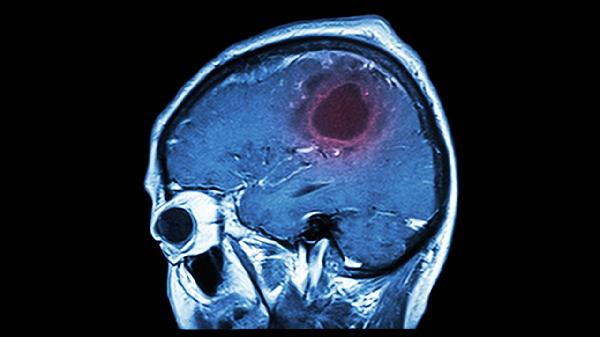

頭部外傷可能導(dǎo)致血管壁受損,初期出血量較少未被檢出,隨著時(shí)間推移血管破裂加劇形成血腫。典型表現(xiàn)為頭痛進(jìn)行性加重伴意識(shí)障礙,需通過(guò)頭顱CT動(dòng)態(tài)監(jiān)測(cè),嚴(yán)重時(shí)需行開(kāi)顱血腫清除術(shù)。

遲發(fā)性顱內(nèi)血腫患者應(yīng)保持絕對(duì)臥床休息,頭部抬高15-30度以促進(jìn)靜脈回流。飲食選擇低鹽、高蛋白流質(zhì)食物,避免用力排便引起顱內(nèi)壓升高?;謴?fù)期可進(jìn)行肢體被動(dòng)活動(dòng)預(yù)防深靜脈血栓,三個(gè)月內(nèi)禁止劇烈運(yùn)動(dòng)。定期復(fù)查頭顱CT監(jiān)測(cè)血腫吸收情況,若出現(xiàn)意識(shí)模糊、肢體癱瘓等新發(fā)癥狀需立即就醫(yī)。